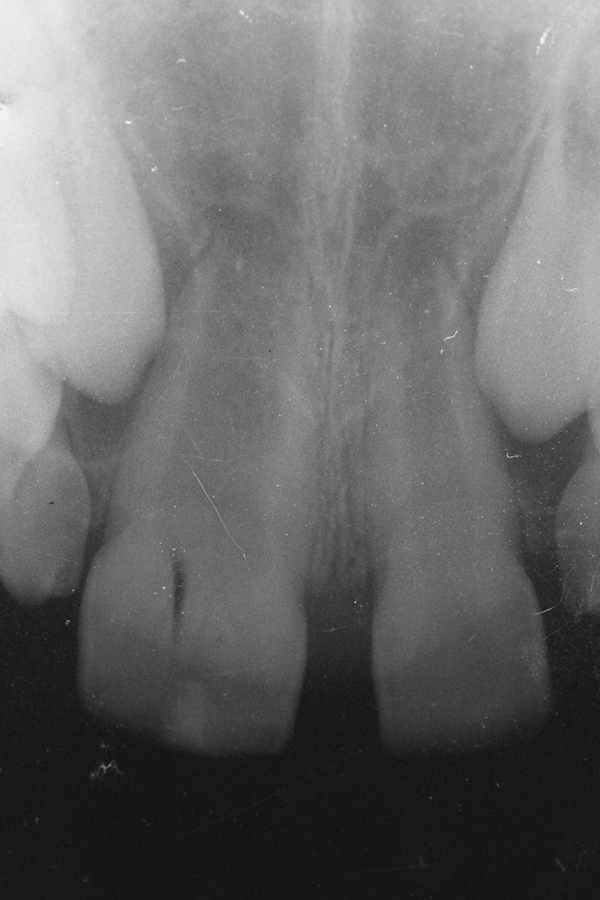

A 9-year-old girl, referred to a prosthodontic office by her pediatric dentist, presented with her mother’s chief complaint: “The kids are teasing her about her big front tooth.” Findings from radiographic and clinical examinations revealed fused maxillary central-peg lateral incisors, teeth Nos. 7 and 8, and a congenitally missing lateral incisor, tooth No. 10 (Figure 1 through Figure 3). An implant was selected as the ideal treatment to replace tooth No. 10 when somatic growth was complete. A diagnostic wax-up was fabricated to determine if the fused tooth could be made to resemble two teeth, using pink composite to give the illusion of an interproximal papilla. The patient was referred for an orthodontic consultation to plan for closure of the diastema between teeth Nos. 8 and 9 and achievement of proper alignment for implant No. 10. The patient was also referred to a periodontist for pretreatment assessment of the tooth No. 10 site. An endodontist was consulted should exposure of the large pulp occur during tooth preparation.

Fig 3. Radiographic scan of fused maxillary central-peg lateral incisors, teeth Nos. 7 and 8, and congenitally missing lateral incisor, tooth No. 10.

Figure 3